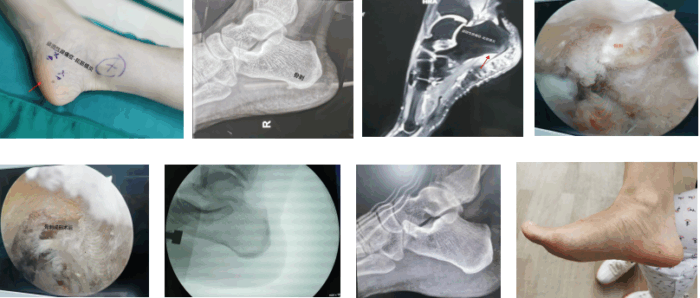

“很多人以为‘跟痛症’只能忍着或必须‘开大刀’,其实这是误区。”孔长庚指出,其实目前微创内镜技术是比较有效的选择。该技术的核心优势在于创伤微小、恢复迅速、并发症风险低。手术仅在患者足踝内侧分别做两个约5毫米的微小切口,组织损伤轻,通过高清内镜直视下松解跖筋膜及病灶清理,疼痛缓解效果显著。

关节镜下跖筋膜松解

依托成熟的关节镜技术积累和先进设备,上海六院海口医院已建立起标准化的微创手术方案,使其成为顽固性跟痛症的常规有效手段。患者术后3天可尝试部分负重,平均3-6周恢复基本行走能力。配合康复训练,复发风险也显著降低。

孔长庚为患者实施内镜下治疗顽固性跟痛症(跖筋膜炎)

2021年10月21日,李女士在医院接受了手术。整个手术过程约30分钟。术后3天,她便在家属的保护下,尝试穿后足减压鞋部分负重站立及短距离行走。“手术后不久,脚后跟那种被紧紧揪着的疼痛感就明显减轻了。”李女士表示。